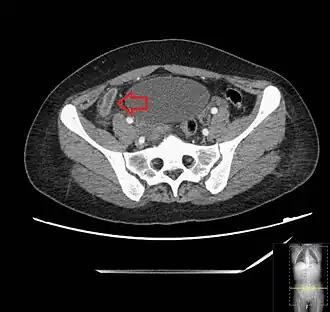

Diagnosis

_(Radiopaedia_154713-127660_Axial_1).jpg)

The physician will ask questions to get the health history, assess the patient's symptoms, do a complete physical exam, and order both laboratory and imaging tests.[36] Appendicitis symptoms fall into two categories, typical and atypical.[37]